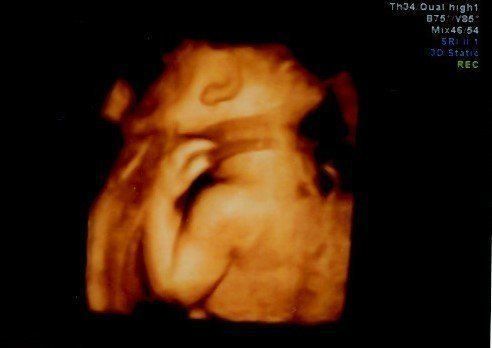

妊娠31週目のエコー写真 3Dエコー画像撮影に再チャレンジ

以前の3D画像撮影で赤ちゃんの顔の撮影ができなかったことがどうしても心残りで、義理の母が上京するタイミングに合わせて再撮影にチャレンジ。病院からは、この時期は赤ちゃんが育ちすぎているので希望通りに撮影できるかわかりません、と言われていました。それでも撮影中は、看護師さんが寝ている赤ちゃんをおなかの上から優しくゆすって顔の位置を変えてくれ、無事撮影することができました。

入院後は次々と襲ってくる激しい陣痛に10時間以上耐えました。そして何度も検査した結果、医師の判断で帝王切開をすることが決定。夫は看護師に促されるままに同意書にサインし、私は即手術台へ。あっという間に4100g、54cmのビッグサイズのわが子が、妊娠40週と5日目に誕生しました。初めて見たわが子の顔は、3Dエコー画像で見たものとそっくり。夫婦で笑ってしまいました。